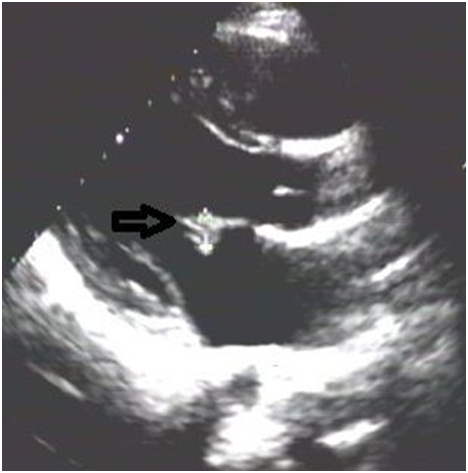

Prostate malignancy was ruled out. Plasma CEA and CA19-9 were normal, stool occult blood negative, upper GI endoscopy showed gastric ulcer with duodenal erosions with biopsy from lesions ruling out malignancy, colonoscopy showed multiple colonic diverticula (Figure 3).

Figure 3 Coloscopy showing colonic diverticuli(arrow).